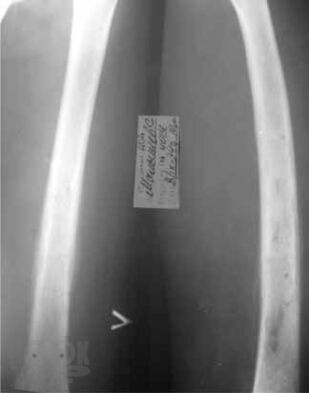

В пособии освещены современные концепции этиопатогенеза наиболее распространенных хирургических заболеваний детского возраста – гнойно-воспалительных заболеваний мягких тканей; различных форм гематогенного остеомиелита; деструктивных пневмоний; бронхоэктатической болезни; гнойно-воспалительных заболеваний мочевыделительной системы и органов брюшной полости – их диагностика и дифференциальная диагностика, современные методы консервативной терапии и оперативного лечения; критерии диагностики сепсиса и принципы рациональной антибиотикотерапии у детей. Пособие предназначено для студентов, обучающихся по специальности «Педиатрия», «Лечебное дело», «Медико-профилактическое дело».